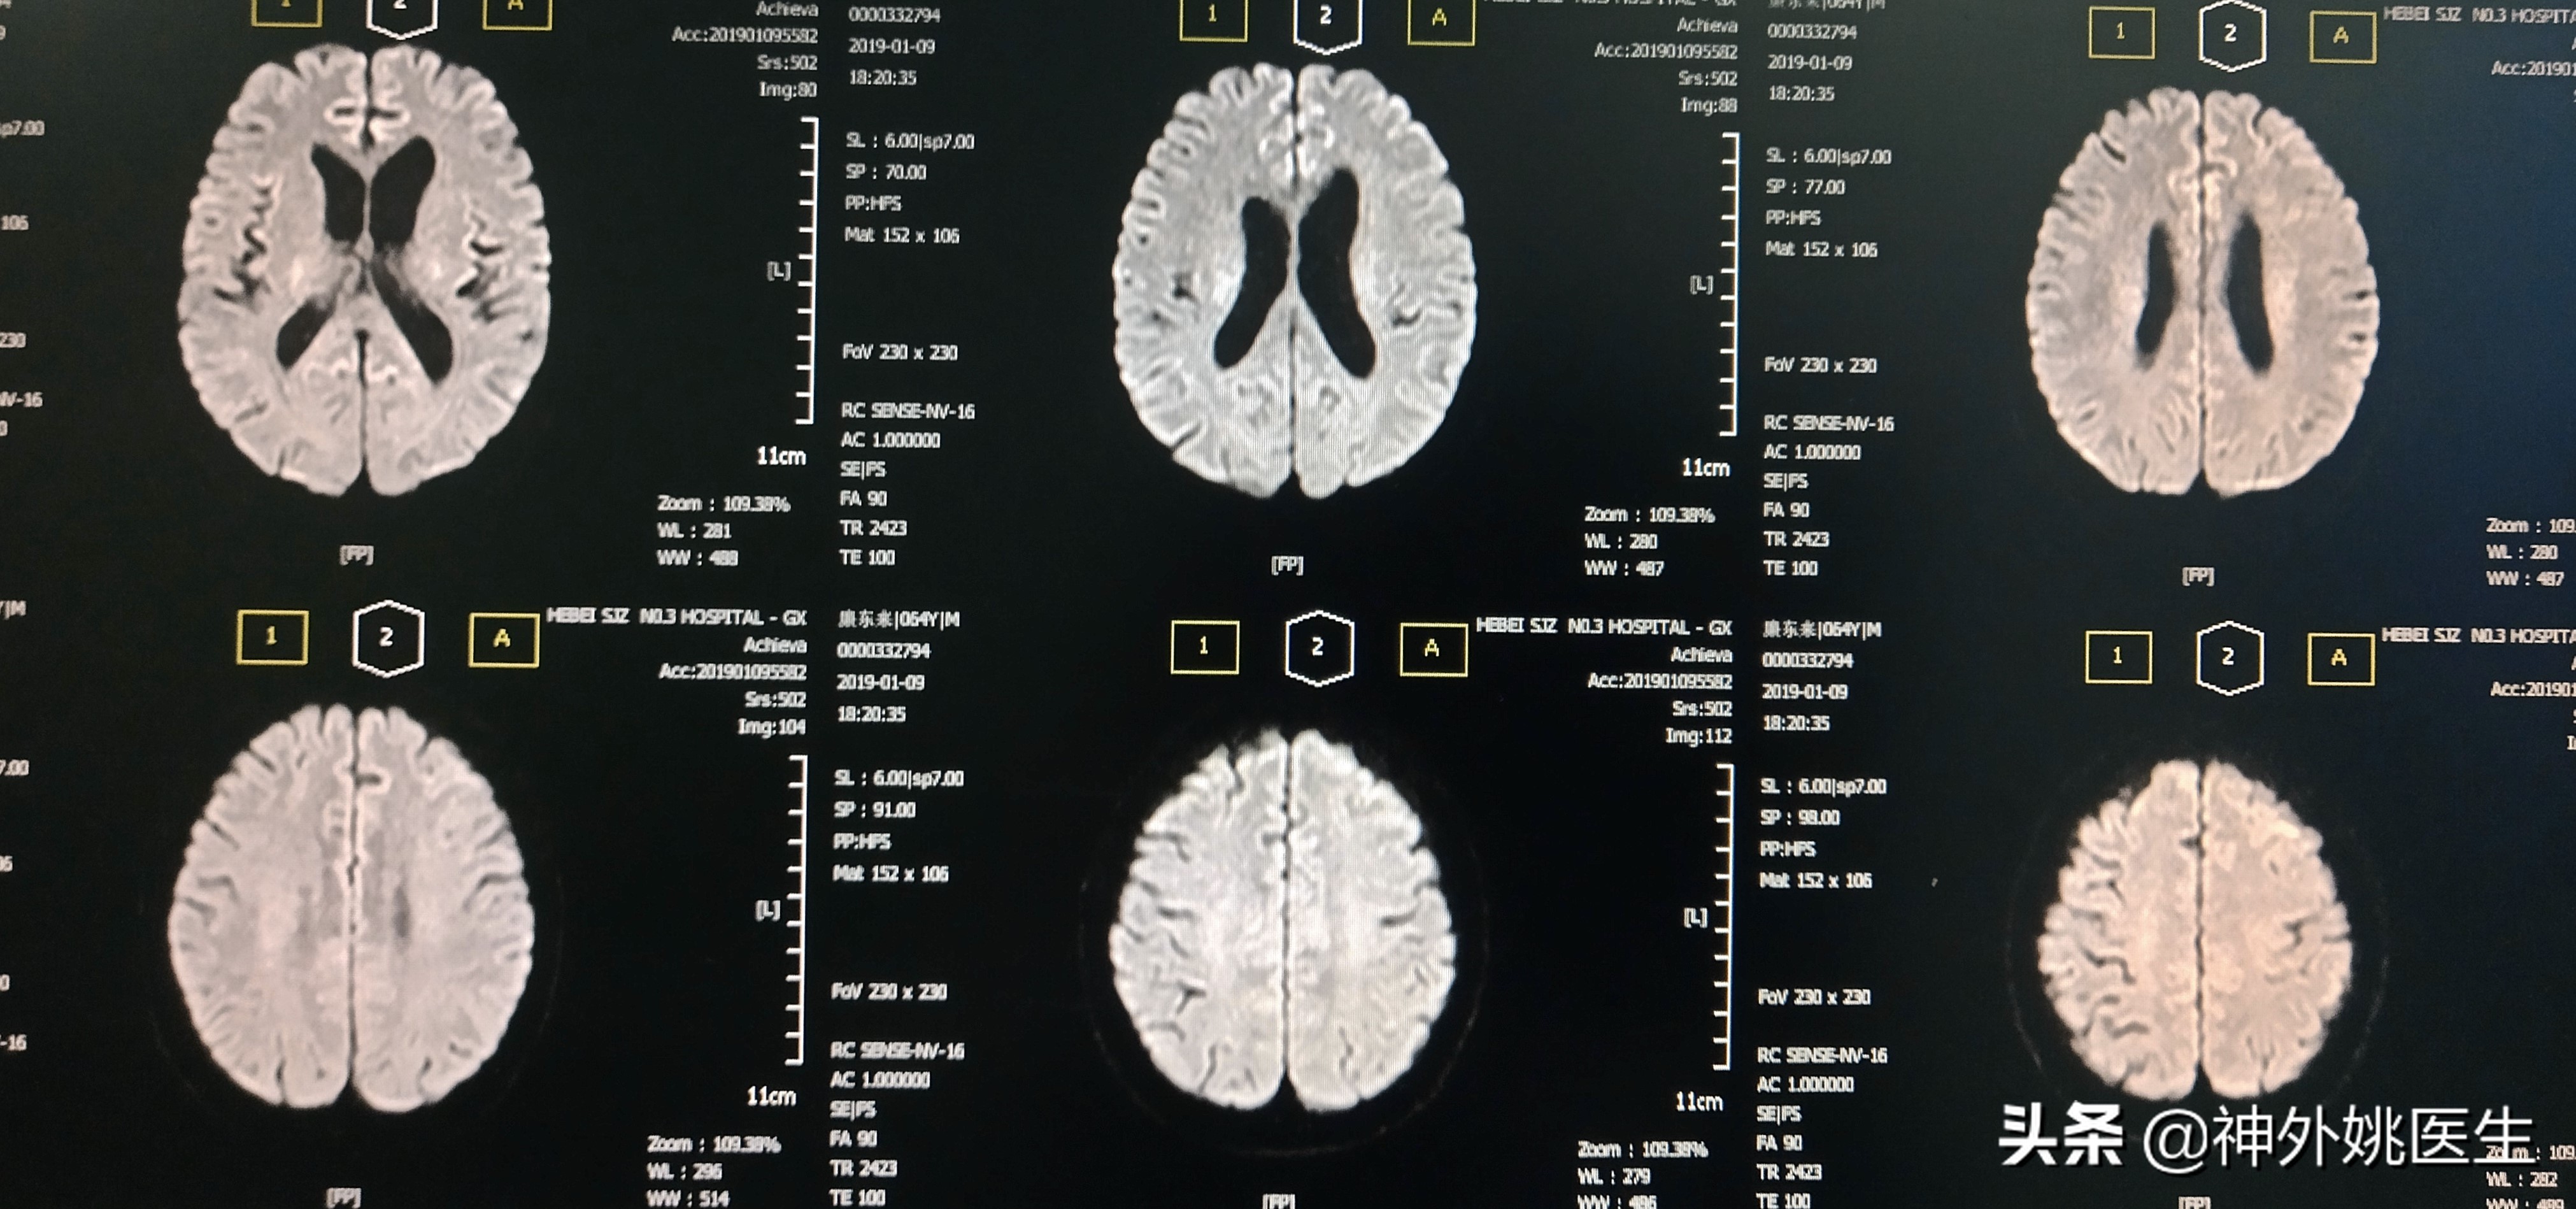

图1 头MRI示双额顶叶及右基底节区缺血灶。